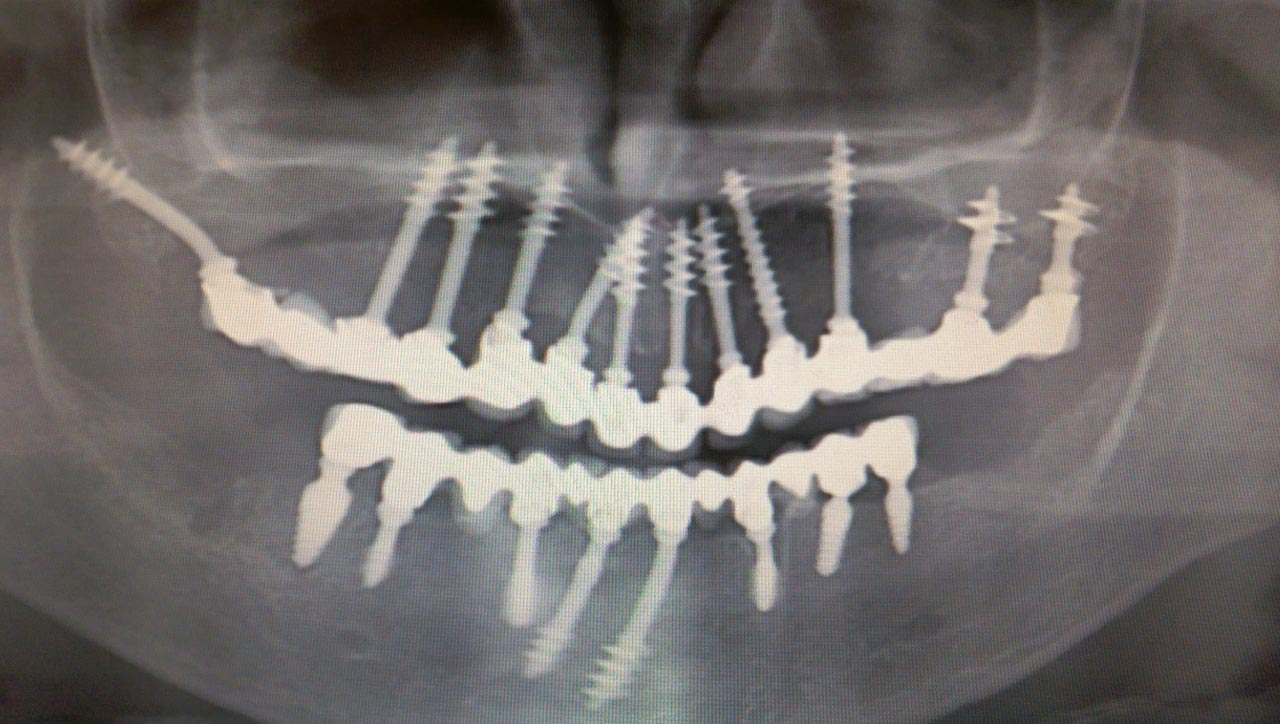

Teljes fogatlanság helyreállítása 2 nap alatt

Teljes fogatlanság helyreállítása 2 nap alatt azonnal terhelhető svájci IHDE implantátumokkal és PMMA műanyag hidakkal. Intraorális szkennerrel vettünk lenyomatot az implantáció után, és erre a digitális mintára készítette el a fogtechnika a hidak digitális tervezését, majd faragta ki műanyagból. Ezt a gyors munkát az azonnal terhelhető implantátumok és a digitális lenyomat, tervezés segítségével tudtuk megcsinálni mindössze 2 nap alatt. Dr. Kelemen Péter és a Symbion Fogtechnika munkája.